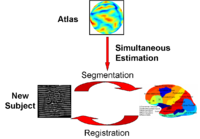

Optimal Atlas Regularization in Image SegmentationWe propose a unified framework for computing atlases from manually labeled data sets at various degrees of “sharpness” and the joint registration and segmentation of a new brain with these atlases. Using this framework, we investigate the tradeoff between warp regularization and image fidelity, i.e. the smoothness of the new subject warp and the sharpness of the atlas in a segmentation application. More... |